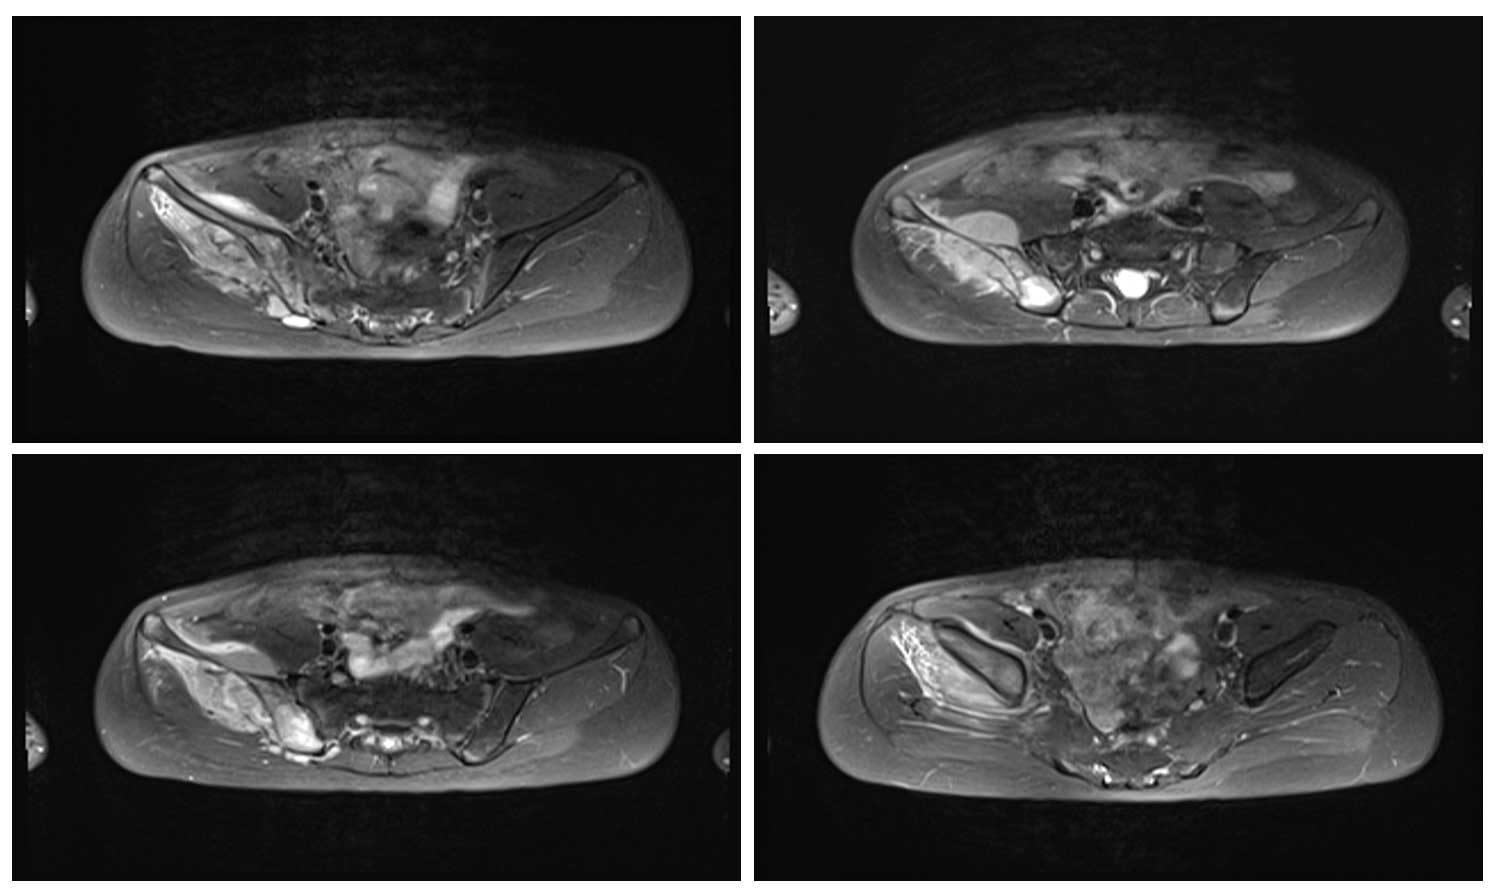

Ameliyat Öncesi: MR’da sağ iliak kanatta yumuşak doku kitlesinin eşlik ettiği tümör dokusu görülmekte.